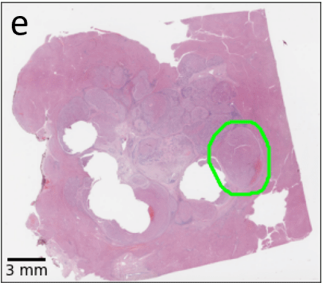

Inverse Problems in Digital Pathology